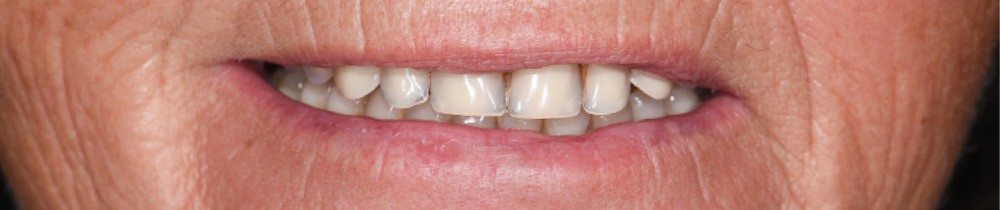

Une patiente de 65 ans consulte pour la perte d’adaptation de sa PACSI lors de la mastication. L’interrogatoire médical ne révèle aucune pathologie ni traitement médicamenteux. La patiente mentionne ne pas fumer et est sérieuse sur le plan prophylactique. Cependant, depuis quelque temps, elle se plaint d’une difficulté à mastiquer associée à une mobilité de sa prothèse et une usure des dents prothétiques (fig. 1a à e).